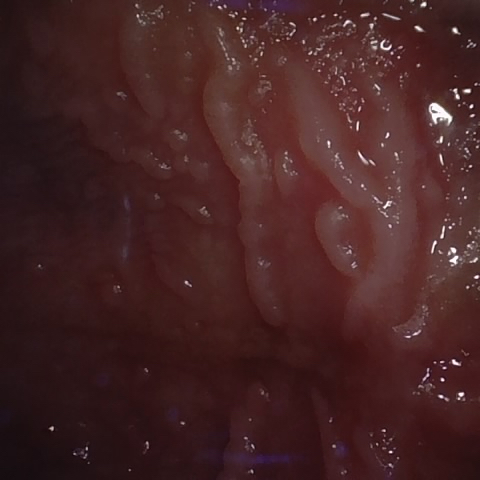

Annotated as "Good"